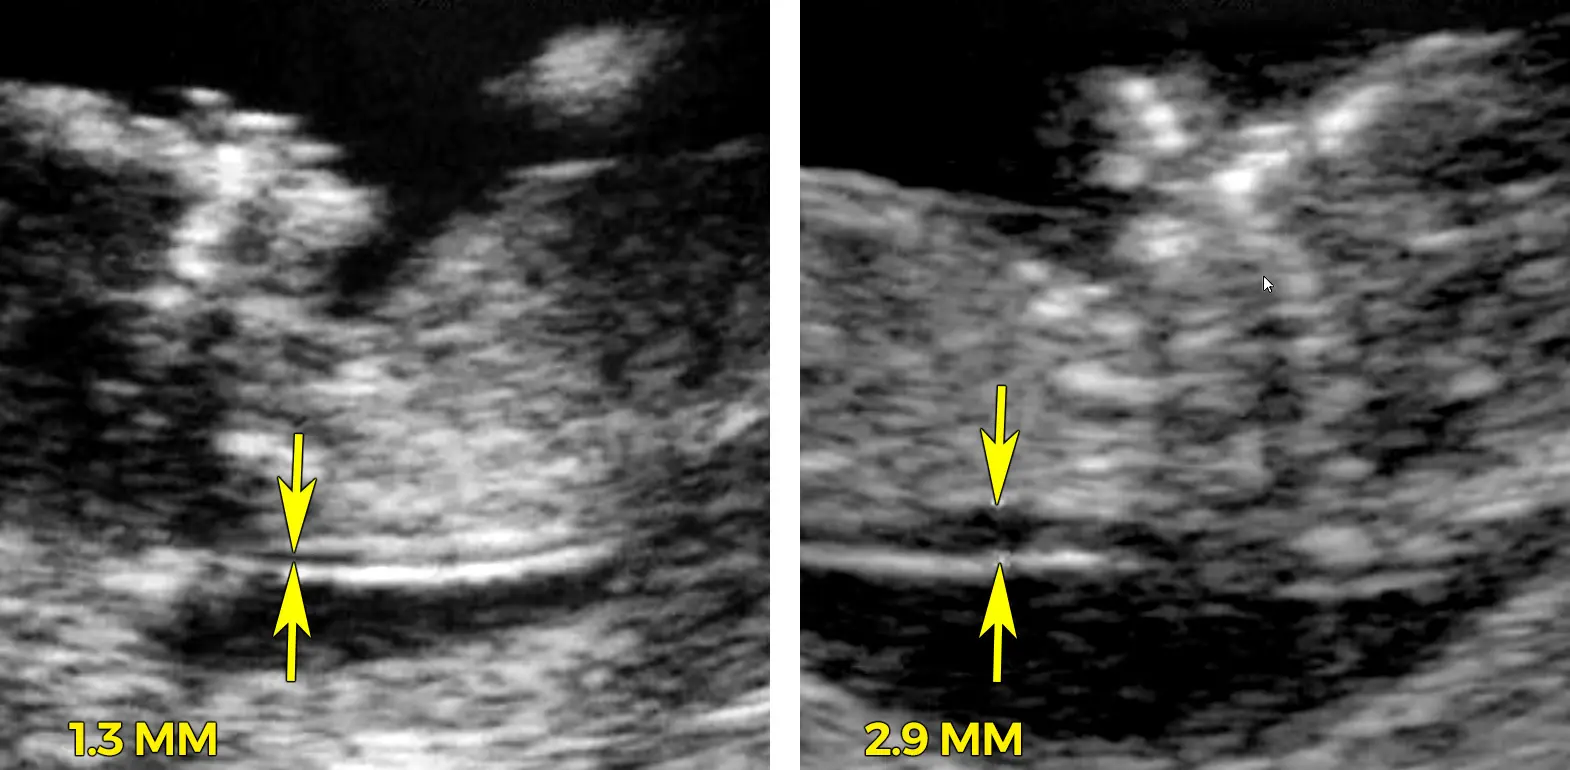

Die Dicke der Nackenfalte variiert von Baby zu Baby. Eine normale Nackenfalte ist in der Regel dünner als 3 mm. Eine dickere Nackenfalte kann jedoch ein Zeichen für eine chromosomale Anomalie sein. Es ist jedoch wichtig zu beachten, dass eine dicke Nackenfalte nicht immer ein Hinweis auf ein Problem ist. Viele Babys mit einer dicken Nackenfalte sind gesund.

Eine normale Nackenfalte ist in der Regel dünner als 3 mm. Eine normale Nackenfalte bedeutet, dass das Risiko für chromosomale Anomalien geringer ist. Es ist jedoch wichtig zu beachten, dass eine normale Nackenfalte nicht immer bedeutet, dass das Baby gesund ist. Es gibt auch andere Faktoren, die das Risiko für chromosomale Anomalien beeinflussen können.

Eine normale Nackenfalte ist in der Regel dünner als 3 mm. Allerdings kann die Dicke der Nackenfalte von Baby zu Baby variieren.